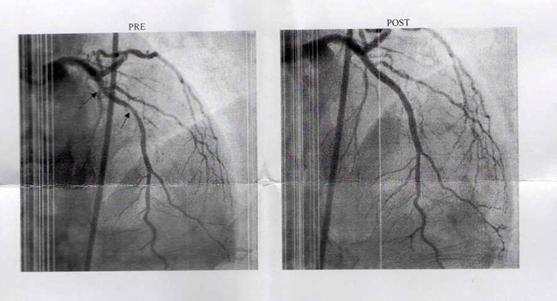

29/11/2018: Spinal Fusion: This

week I am having four-level spinal fusion on my lumbar spine (irrevocably

damaged by tough hard heavy work from when I was only a child). However, the

surgeons have found one disc which is sound so I can have this done, be free of

pain and just be a little stiffer getting out of my sleeping bag in the

mornings – indeed I might even move to a quilt as the docs are limiting me to

5kg for the next couple of months. That will certainly make me the ultralight

hiker! I will find an X-ray of my spine to illustrate this post, but I am in

hospital suffering all manner of indignities and cruelties just now so posts

are a bit light. Sorry.

I have two of the best spinal surgeons in Australia working on me: Dr

Caroline Tan and Dr David Edis. I had the discs removed on Tuesday and replaced

with plastic inserts through my side in a procedure known as OLIF. This is

apparently the best way to do it. Then on Friday the surgeons will go in though

my back to insert the rods and screws which will hold the vertebrae until they

fuse. They paint a highly sophisticated artificial chemical construct on the

area to create this bone growth and fusion (which will take up to about 3

months).